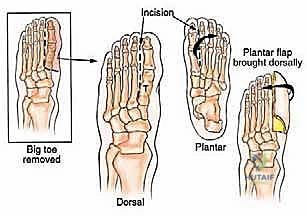

Metatarsophalangeal Joint Amputation

- Incision Planning: A longer plantar flap is planned. The incision is carried out at the level of the metatarsophalangeal joint on the dorsum of the foot.

- Dissection: Using sharp dissection, expose the MTP joint.

- Joint Disarticulation: The capsule, collateral ligaments, and flexor/extensor tendons are sharply cut at the level of the joint.

- Vascular Control: The digital vessels are identified and meticulously cauterized.

- Amputation: The toe is then removed.

- Flap Closure: The long plantar flap is brought over the dorsal aspect of the metatarsal head. The skin is repaired using 4-0 nylon sutures in an interrupted fashion, creating a smooth, non-tender, end-bearing stump.